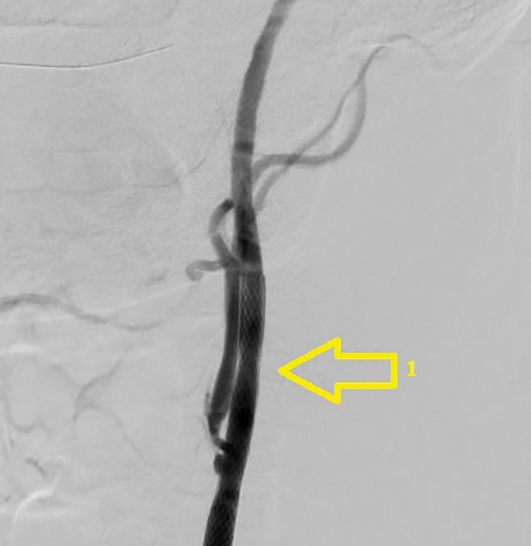

Перед вмешательством больной получил нагрузочную дозу клопидогреля (300 мг). Первым этапом в эндоваскулярной операционной выполнялось ЧКВ ПНА. Введено 10 тыс. ЕД гепарина внутриартериально. Через трансфеморальный доступ справа (интродьюсер 6F, катетер 6F) был установлен стент с лекарственным покрытием «Endeavor Resolut» («Medtronic», США) (рис. 5). Далее через тот же доступ (катетер 6F) с использованием дистальной защиты («Filter Wire EZ», «Boston Scientific Corporation») проведена каротидная ангиопластика со стентированием левой ВСА, установлен стент «RX Acculink» («Abbot Vascular») (рис. 6). После завершения процедуры больной был транспортирован в сосудистую операционную. Время между ангиопластикой и началом КЭЭ составило 30 мин. Под эндотрахеальным наркозом (введено дополнительно 5 тыс. ЕД перед пережатием ВСА) выполнена классическая КЭЭ справа с пластикой зоны реконструкции заплатой из диэпокси- обработанного ксеноперикарда. Время пережатия артерий составило 25 мин. Послеоперационный период протекал без особенностей. Клиника стенокардии не рецидивировала. По данным цветного дуплексного сканирования брахиоцефальных артерий признаков рестеноза, увеличения скоростных показателей в ВСА с 2 сторон не определяется. Пациент выписан на 7-е сутки после операции в удовлетворительном состоянии. Рекомендован приём двойной дезагрегантной терапии (клопидогрель 75 мг + ацетилсалициловая кислота 125 мг).

Рис. 6. Каротидная ангиопластика со стентированием левой ВСА: 1 — установленный стент. / Fig. 6. Carotid angioplasty with left ICA stenosis: 1 — installed stent.